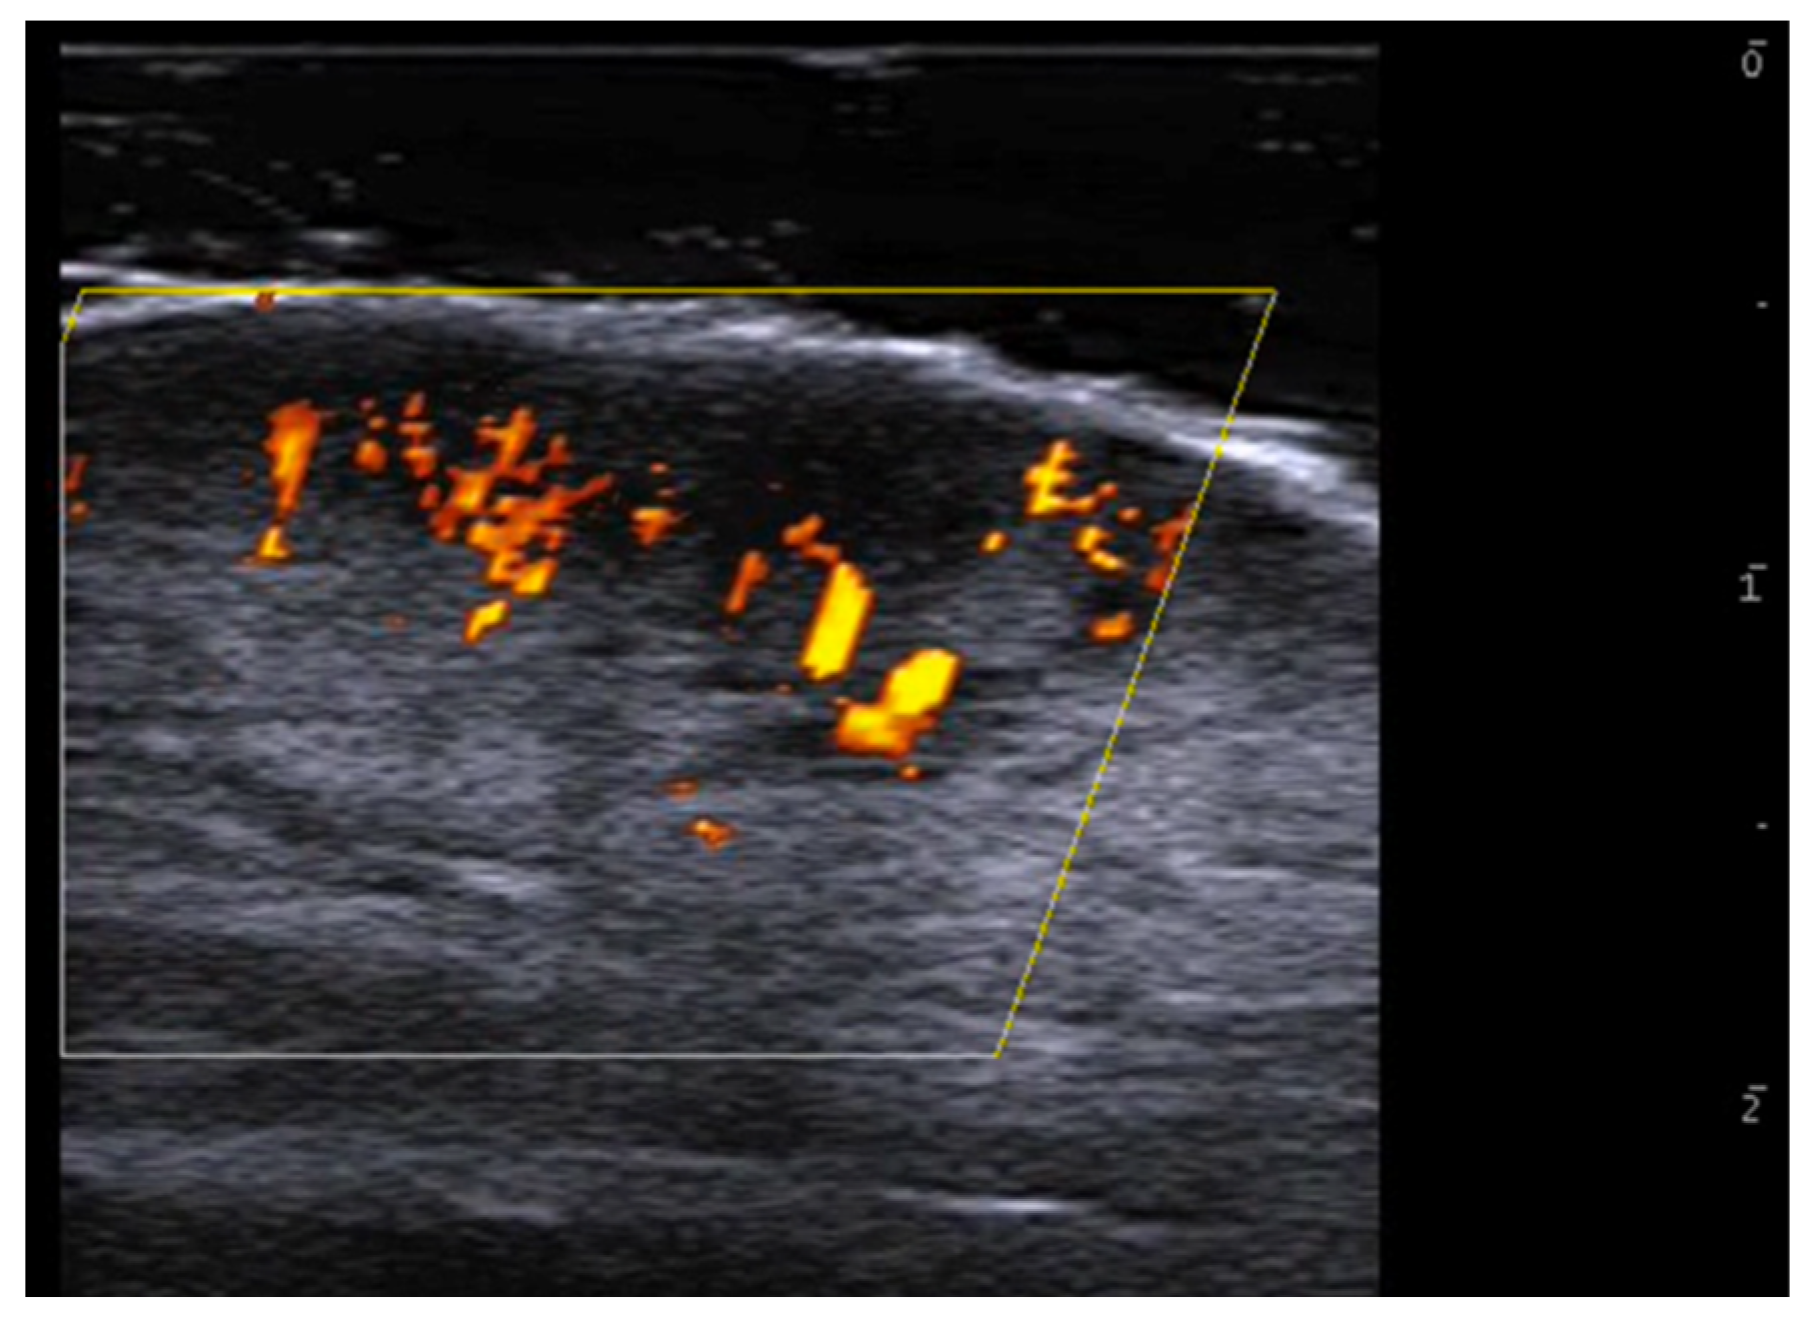

5. Specific Cutaneous Structure and Sites of Skin Disorders